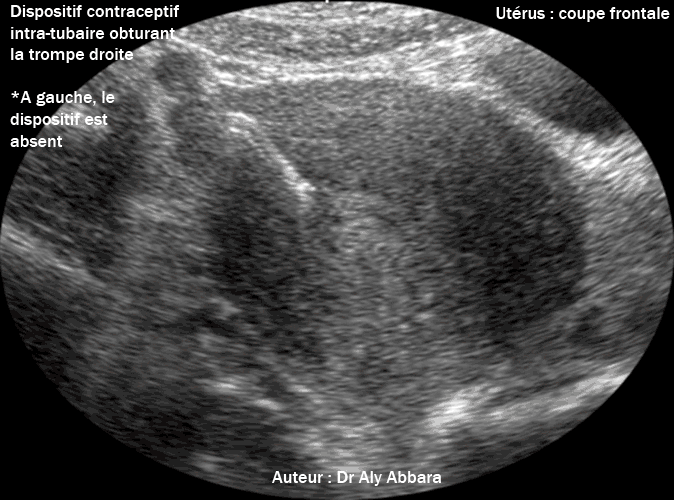

L'aspect échographique du dispositif contraceptif intra-tubaire qui fut introduit dans la trompe deux ans auparavant. Il s'agit d'une coupe frontale de l'utérus mettant en évidence le fond utérin. On remarque la disparition du dispositif intra-tubaire du côté gauche. |